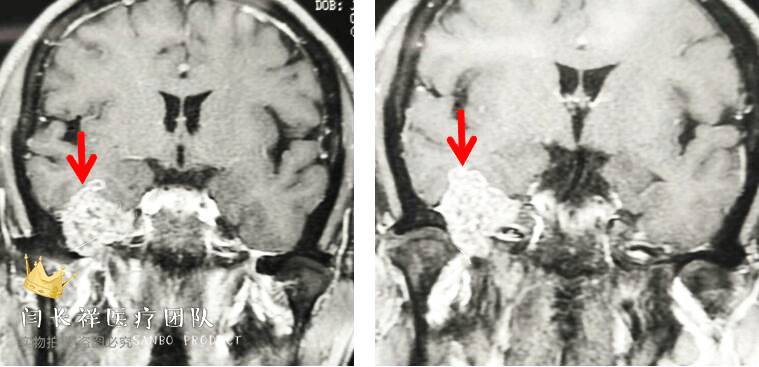

中颅窝-颞下窝占位

术前冠位CT示右侧中颅窝、颞下窝、翼腭窝占位,病灶呈稍高密度。

术前冠位CT骨窗像示右侧中颅窝底骨质被肿瘤侵蚀破坏。